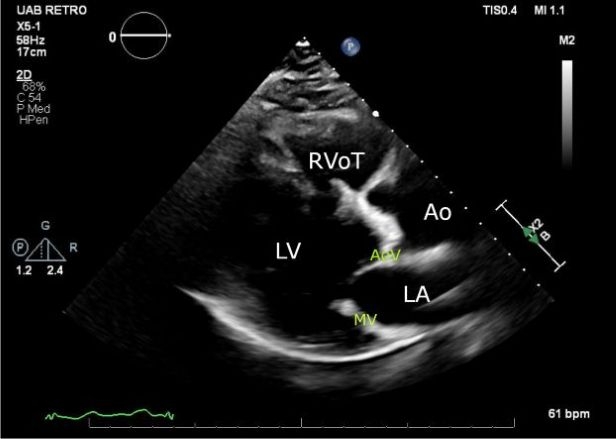

A 74-year-old male developed severe intraoperative vasoplegia following surgical aortic valve replacement, ascending aortic replacement, and coronary artery bypass grafting. He was separated from cardiopulmonary bypass without issue, but cardiopulmonary collapse occurred with transfusion of protamine, fresh frozen plasma, and platelets. He was treated for presumed anaphylaxis with inotropes, steroids, and angiotensin II. While this collapse was initially attributed to transfusion reaction, subsequent investigation revealed a diagnosis of AGS. He was treated with diet restrictions and omalizumab outpatient and his bioprosthetic valve has demonstrated no signs of early failure.

AGS should be considered in anaphylactic patients who receive intra-procedural heparin. The manifestation of alpha-gal-related allergies is uniquely inconsistent in timing and severity. Long-term clinical and echocardiographic surveillance are warranted to monitor for accelerated coronary disease and early bioprosthetic failure.